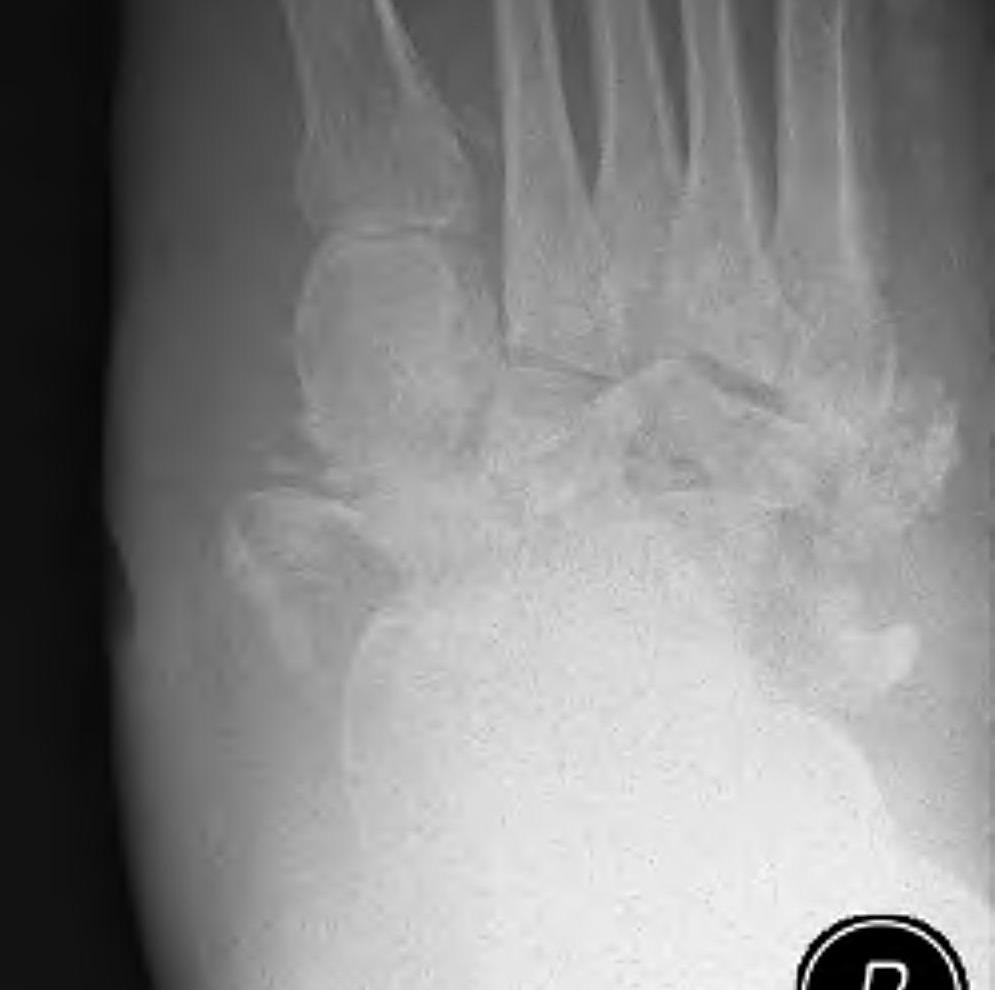

Demineralisation of regional bone Periarticular fragmentation Joint dislocation |

Midfoot dissolution, coalescence and reconstruction

Midfoot collapse

Midfoot collapse with subluxation of midtarsal joints